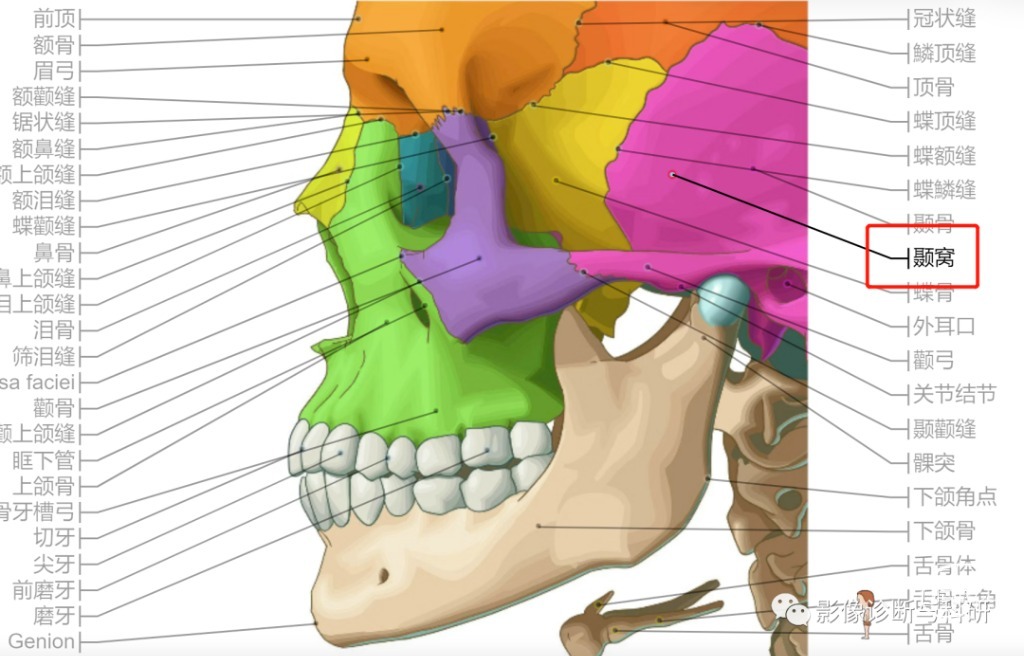

翼窝、颞窝、颞下窝、翼腭窝

2、颞窝

3、颞下窝

翼外板与下颌骨升支之间,边界(内:翼突、翼腭窝;外:下颌升支 ;前:上颌窦后壁;后:茎突)。 内含颞肌、咀嚼肌、腮腺深叶及下颌骨喙突等。可上经颧弓深面与颞窝相通,向前经眶下通眶,向内经翼上颌裂通翼腭窝。颞下窝还向上经卵圆孔和棘孔与颅中窝相通。颞下窝内容纳的主要结构为翼外肌、翼内肌、三叉神经的下颌神经分支、面神经的分支鼓索、耳神经节、上颌动脉和翼静脉从。